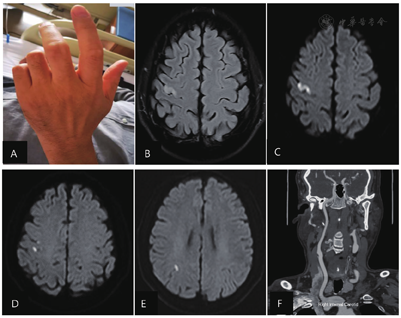

患者男性,57岁,因"左手活动不利8 h"于2022年3月9日入院。患者自述于当日8 h前无明显诱因突发左手活动不灵,表现为左手指固定不能活动,呈现"爪形手"(图1A),无腕下垂表现,不伴其他肢体活动不灵表现,无头晕、言语障碍,无饮水呛咳、声音嘶哑、视物双影,无发热、抽搐、尿便障碍。发病后就诊于秦皇岛市第一医院门诊,颅脑CT未见确切异常,诊断为脑梗死收住秦皇岛市第一医院神经内科。既往有高血压史15年,最高血压不详,平素口服苯磺酸左旋氨氯地平(2.5 mg,1次/d),血压控制在130/80 mmHg(1 mmHg=0.133 kPa)左右。否认糖尿病、高脂血症、冠心病、心房颤动和肿瘤病史,否认吸烟、饮酒史。

左手表现为"爪形手"(A);颅脑MRI液体衰减反转恢复序列示右侧中央前回手结节区高信号(B);颅脑MRI弥散加权成像示右侧手结节区病变(C)、右侧中央沟和中央后回病变(D)和右侧角回边缘病变(E);颅脑CT血管造影显示右侧颈内动脉分叉处斑块(F)

入院后给予双重抗血小板、稳定斑块、改善循环和清除自由基等治疗。次日复查颅脑MRI和磁共振血管成像示右侧多发性急性脑梗死(图1B~E),血管动脉粥样硬化表现,椎基底动脉延长扩张。血尿便常规、肝肾功能、血糖、电解质、凝血功能、抗心磷脂抗体、风湿检验、抗核抗体谱、肿瘤标志物、甲状腺功能未见明显异常。总胆固醇和低密度脂蛋白胆固醇水平升高。胸部CT、动态心电图、心脏彩超、右心声学造影未见异常。颈部血管彩超示双侧颈动脉内膜不规则增厚伴右侧混合性斑块形成,双侧椎动脉未见异常。头颈部CT血管造影示右侧颈总动脉分叉处可见混合性斑块影,狭窄程度<29%(图1F),基底动脉延长扩张。双上肢肌电图未见明显异常。

患者于2022年3月11日左手桡侧拇指和食指能够正常活动,尺侧小指和环指内收、外展和屈伸困难。查体:左手环指和小指内收肌肌力3级,伸肌肌力4级,屈肌肌力3级,外展肌肌力4级。3月17日出院时,左手功能基本恢复,小指和环指屈伸、内收、外展肌肌力4级,余手指肌力5级,改良Rankin量表评分(modified Rankin Scale, mRS)0分。出院后继续双重抗血小板治疗21 d,同时接受稳定斑块、控制血压和改善侧支循环治疗。2022年4月7日复诊自觉左手活动笨拙,环指背伸和外展受限。查体:环指背伸和外展肌肌力4级,余手指肌力5级,mRS评分0分。

手结节区受累的常见临床症状表现为桡侧手麻痹、尺侧手麻痹或完全手麻痹,伴或不伴有腕下垂及感觉障碍[12],但有时也可单纯表现为食指麻痹[13]。关于全手均匀麻痹类型,文献报道的受累病变结构多为条形梗死,累及倒置"Ω"区整个桡臂侧或局限于其上方或结节区广泛受累[14]。病例1表现为"爪形手",在发病初期左手指不能完成屈伸、内收和外展动作,颅脑MRI可见病灶范围较大,累及整个手结节区(图1B和C);病例2累及整个桡臂侧及上方并伴有腕下垂(图2A和B)。此外,病变累及中央沟底部以及中央前回后缘也有报道[15]。除手结节区受累外,功能MRI发现中央后回受累也可引起手部运动障碍[3]。对这种现象的解释,首先是中央后回出现中央前回特有的锥体细胞,其次是中央后回有助于锥体束形成,并可被运动任务的传出部分激活。此外,当手及手指执行运动任务(位置变化)时,需要本体感觉和浅感觉通路参与,也表明中央后回参与其中[12]。病例1和病例2的病变范围均累及中央后回(图1D和图2B),但并未出现感觉障碍,考虑与发生中央后回转换有关。病例1尺侧麻痹恢复延迟,可能与对应的中央后回病变有关。恢复过程中自感活动笨拙,考虑不仅由于运动尚未完全恢复,也与中央后回受累有关。引起孤立性手麻痹的解剖结构还有顶叶、角回白质、丘脑腹后外侧核、内囊后肢、放射冠和脑桥基底部的散在卒中[16],这些部位病变支持广泛分布的大脑区域参与了手的运动控制[17],形成了手控制网络中枢。其中,躯体感觉皮质、顶叶和初级运动皮质形成了皮质间网络连接[2]。更靠后的顶叶病变会在复杂感觉、精确抓握、操作和探索性手指运动方面出现明显障碍[18]。感觉整合可同步激活空间分布的各个皮质[18]。Timsit等[19]报道了3例角回受累引起的孤立性手麻痹。一般表现为轻度力弱,角回通过视觉运动转换控制手部运动,影响对侧手的尺侧力量控制、精细运动和操作[12]。病例1并未发现通过视力改变能改善手的灵活性,可能因为病变靠近角回边缘区(图2E),而且病灶较小,尚未引起临床表现。相关研究表明,发生手局部受累和完全麻痹的比例各占50%[14],手结节区受累占66%,中央后回受累占25%[12],角回受累罕见。

确定梗死的确切机制比较困难,尤其对于这种较小的表浅病变,须特别注意考虑动脉-动脉栓塞[5],还应考虑血流动力学机制导致大脑中动脉和大脑前动脉末端供血区的栓子清除障碍,以及其他原因栓塞,例如肿瘤相关性梗死和空气栓塞[20,21]。根据既往病例报道,手部单瘫患者常存在动脉粥样硬化(84%)、高血压(80%)、高脂血症(68%)、吸烟(40%)、糖尿病(20%)和心房颤动(12%),80%的患者存在≥3个危险因素;最终按照病因学分型归类为大动脉粥样硬化占48%,其他原因占16%,不明原因占36%[1]。本文的病例1和病例2均存在3个危险因素,前者为高血压、高脂血症和右侧颈内动脉轻度狭窄(图1F),后者为高血压、糖尿病和多支脑血管重度狭窄(图2C)。病例数较多的3项研究显示,栓塞占比较高,为62%~82%,其中动脉-动脉栓塞占50%以上[4]。除上述原因之外,还需要关注肿瘤相关性栓塞和卵圆孔未闭。病例1的动态心电图、心脏彩超、右心声学造影和肿瘤标志物等检查未见心脏栓子和肿瘤证据,头颈部CT血管造影示右侧颈内动脉起始部不稳定斑块,考虑为动脉-动脉栓塞机制引起的脑梗死,病例2同样考虑为动脉-动脉栓塞所致,这与既往的病例报道大致类似[22,23]。